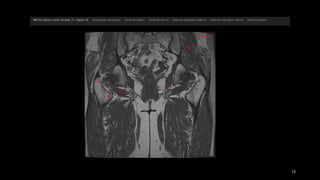

• el tensor de la fascia lata (Tfn y el

sartorio (Sa) se originan en la espina

ilíaca anterosuperior (flecha recta).

• recto femoral (Rf se origina en la

espina ilíaca anteroinferior (punta de

flecha) ,

• músculos ilíaco y psoasilíaco convergen

en un tendón común en un punto

distal que se inserta en el trocánter

menor (flecha curva).

• músculo pectíneo (Pe)

• rama superior del pubis (Pb).

• el tensorde la fascia lata (Tfn y el sartorio (Sa) se originan en la espina ilíaca anterosuperior (flecha recta). • recto femoral (Rf se origina en la espina ilíaca anteroinferior (punta de flecha) , • músculos ilíaco y psoasilíaco convergen en un tendón común en un punto distal que se inserta en el trocánter menor (flecha curva). • músculo pectíneo (Pe) • rama superior del pubis (Pb).

• músculo glúteomayor (GMa) • músculo tensor de la fascia lata (Tfl anterior y la fascia lata (FL) situada entre ambos músculos • «bandeleta de Massiat» (BM) • glúteo medio (GMe) y glúteo menor (GMI) • trocánter mayor (TM)

• #62  Características anatómicas de los músculos y tendones de la región anterior de la cadera. Dibujo de una vista anterior de la cadera que ilustra las relaciones entre los músculos anteriores. En el plano superficial, el tensor de la fascia lata (Tfn y el sartorio (Sa) se originan en la espina ilíaca anterosuperior (flecha recta). En un plano más profundo, el recto femoral (Rf se origina en la espina ilíaca anteroinferior (punta de flecha). Obsérvese que los músculos ilíaco y psoasilíaco convergen en un tendón común en un punto distal que se inserta en el trocánter menor (flecha curva). En dirección medial al tendón del psoasilíaco, se observa el músculo pectíneo (Pe), que se inicia en la cara anterior de la rama superior del pubis (Pb).

• #63  Características anatómicas de las estructuras paraarticulares de la región externa de la cadera. a) dibujo de una vista lateral de la cadera, que muestra la capa superficial de músculos y la fascia lata. El conjunto de músculos llamado «deltoides de Farabeuf» está formado por el gran músculo glúteo mayor (GMa) posterior, el músculo tensor de la fascia lata (Tfl anterior y la fascia lata (FL) situada entre ambos músculos. Obsérvese la «bandeleta de Massiat» (BM), que representa un engrosamiento focal de la fascia lata que se inserta en la porción anterior de la cresta ilíaca. b) Dibujo de una vista lateral de la cadera que muestra la capa profunda de músculos. Las estructuras superficiales mostradas en a) se muestran aquí semitransparentes. Obsérvese las relaciones entre los músculos glúteo medio (GMe) y glúteo menor (GMI) situados justo por debajo de la fascia lata y de la porción anterior del músculo glúteo mayor. El músculo glúteo menor se encuentra situado por delante del glúteo medio y en un plano profundo con relación a éste. Ambos músculos se insertan en el trocánter mayor (TM).